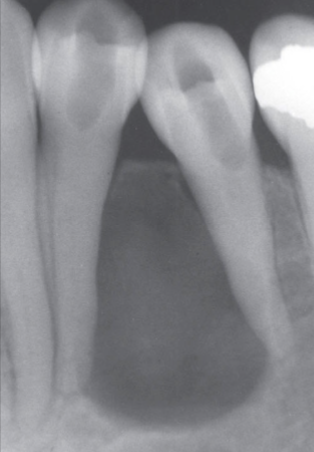

What is the dental anomaly?

Healing Cyst

What are the Radiographic Characteristics of this Healing Cyst?

New bone forms at the original cortex and grows toward the center